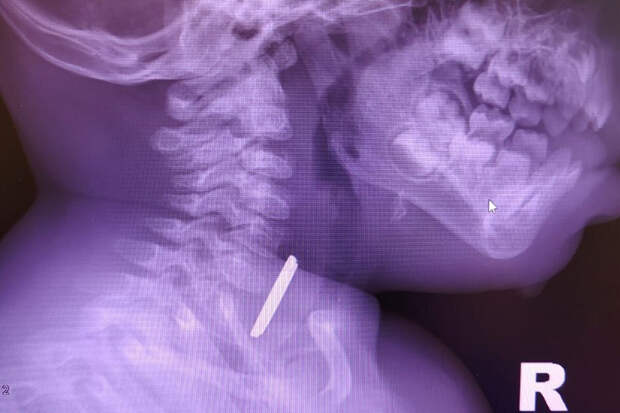

Маленький пациент поступил в больницу с затрудненным глотанием и слюноотделением. Ребенка направили на рентген, который показал наличие батарейки в верхней трети пищевода.

Пациента направили направили на экстренную операцию, и под наркозом извлекли предмет, который уже успел причинить здоровью младенца вред."Батарейка повредила стенку пищевода, вызвав глубокий электрохимический ожог, занимающий половину просвета пищевода. Учитывая тяжесть состояния от полученной травмы, ребенок был госпитализирован в отделение реанимации, где проводилась интенсивная терапия", - рассказал детский хирург детской больницы Вячеслав Воронин.